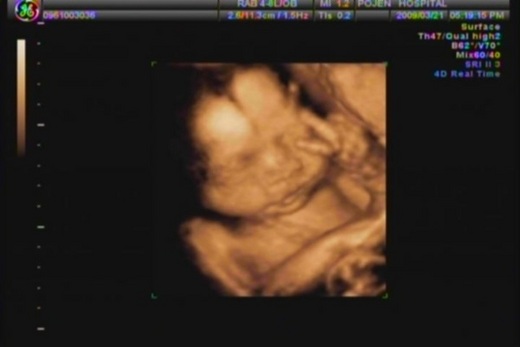

98.03.21...Nemo廿六週了

第二次的4D超音波,這週的Nemo看起來更有肉了呢!但我始終覺得看起來和第一次是不同的人,但阿嬤和把拔都不覺得說。這次Nemo很合作,很容易就讓我們看到他的臉,不曉得是鏡頭關係還是怎樣的,感覺臉好膨皮哦!

而且這次Nemo很可愛哦!會比YA,也會比"棒

"還會打哈欠和笑呢!不曉得是夢到了什麼這麼高興,所以PO上他在比YA的照片,由於是從影片中截取的,所以有點小模糊,但還是卡哇伊的啦!